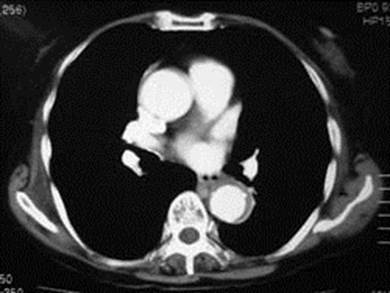

図1 偽腔開存A型。心嚢液貯留ならびに下行大動脈の二腔構造が認められる

確定診断はCT検査により行います。CT画像から、解離の存在だけでなく、解離の形態、進展、エントリー・リエントリーの同定、さらには破裂や臓器虚血の有無を評価します (図1)。単純CT、造影CT(早期相および後期相)の撮像が基本です。